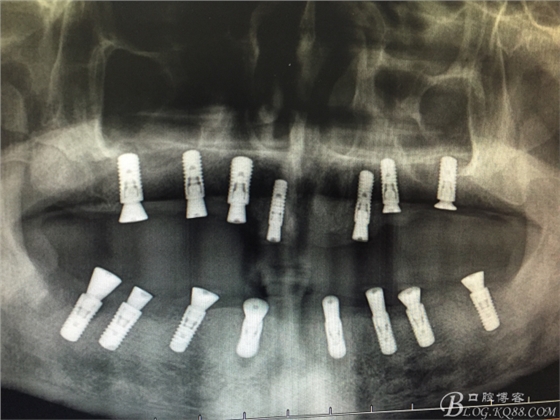

患者37歲 男 全口牙周病 手術(shù)一次完成 全程3小時(shí)全口種植修復(fù)全口種植修復(fù)全口種植修復(fù)全口種植修復(fù)全口種植修復(fù)全口種植修復(fù)全口種植修復(fù)全口種植修復(fù)全口種植修復(fù)全口種植修復(fù)全口種植修復(fù)全口種植修復(fù)全口種植修復(fù)全口種植修復(fù)全口種植修復(fù)